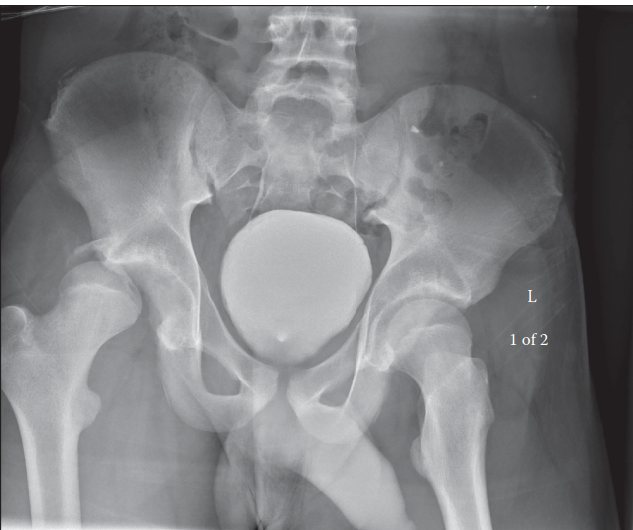

- AP Pelvis X-ray: Confirms the diagnosis of hip dislocation. The femoral head will appear superior and lateral to the acetabulum, with internal rotation of the femur (lesser trochanter not visible). Evaluate for associated pelvic ring injuries or sacral fractures.

Illustration of a posterior hip dislocation, demonstrating the typical position of the femoral head posterior and superior to the acetabulum, highlighting the anatomical relationship with surrounding structures. This view would be consistent with what is encountered during open reduction via a posterior approach.